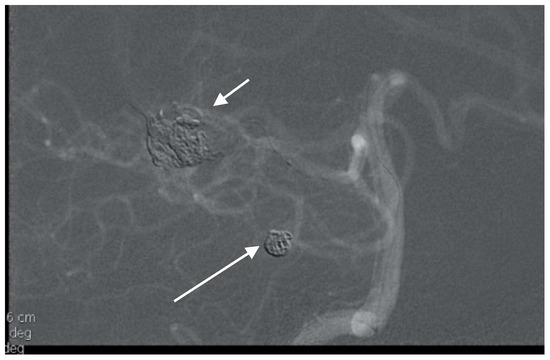

A 50-year-old man presented with a headache. Magnetic resonance imaging (MR) and angiography showed cerebellar AVM and two aneurysms on the right side of the PICA (Figure 6 and Figure 7). The patient underwent an operation, and AVM was successfully resected with both aneurysms clipped. The control angiogram showed good result of the treatment (Figure 8), the postoperative course was without complication, and the patient was discharged.

Figure 7. Lateral angiogram showing cerebellar AVM and two PICA aneurysms.